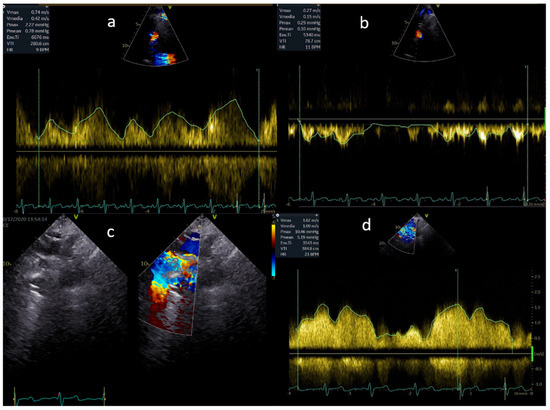

The lack of a subpulmonary ventricular pump results in non-pulsatile flow in the pulmonary vascular bed and Fontan pathway. As a result, the fluid dynamics of the stenoses will be more like a venous obstruction, and the Doppler flow gradient is frequently low. Therefore, the size of the Fontan connection and of the pulmonary arteries should be carefully examined. Any reduction and enlargement downstream should be taken into consideration and studied by both a continuous and a pulsed wave Doppler (Figure 2). A reduction in the variability of flow and a mean gradient as low as 3 mmHg can reflect a significant obstruction.

Figure 2. (a,b) Normal flow in the Fontan pathway; (c,d) mild flow acceleration through a stented extracardiac conduit.